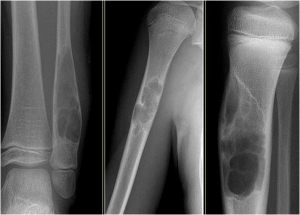

Ung thư xương là một bệnh lý ác tính thường gặp ở thiếu niên và [...]